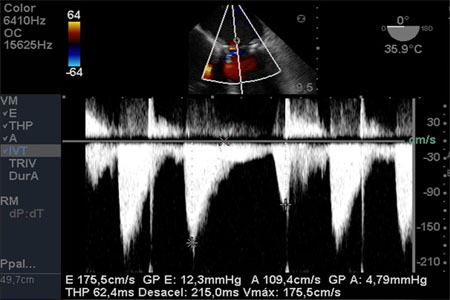

Con Doppler color se evidencia una mínima insuficiencia transprotésica.

El Doppler continuo transprotésico demostró velocidades dentro del rango normal.